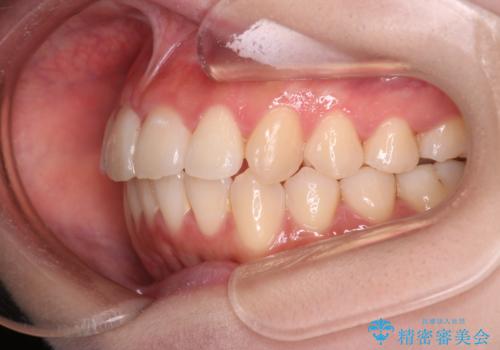

【インビザライン】マウスピースで開咬改善

- 開咬を主訴に来院されました。

IPR(歯と歯の間を削る処置)と顎間ゴムを行いながら、インビザラインで開咬を治療する計画を立てました。

治療をしながら、MFT(口腔筋機能療法)も行っていくことにしました。

歯の移動量が多いケースでしたが、患者様にマウスピースの使用とゴム掛けを頑張っていただいたので

リファイメント1回のみで治療を終わることができました。